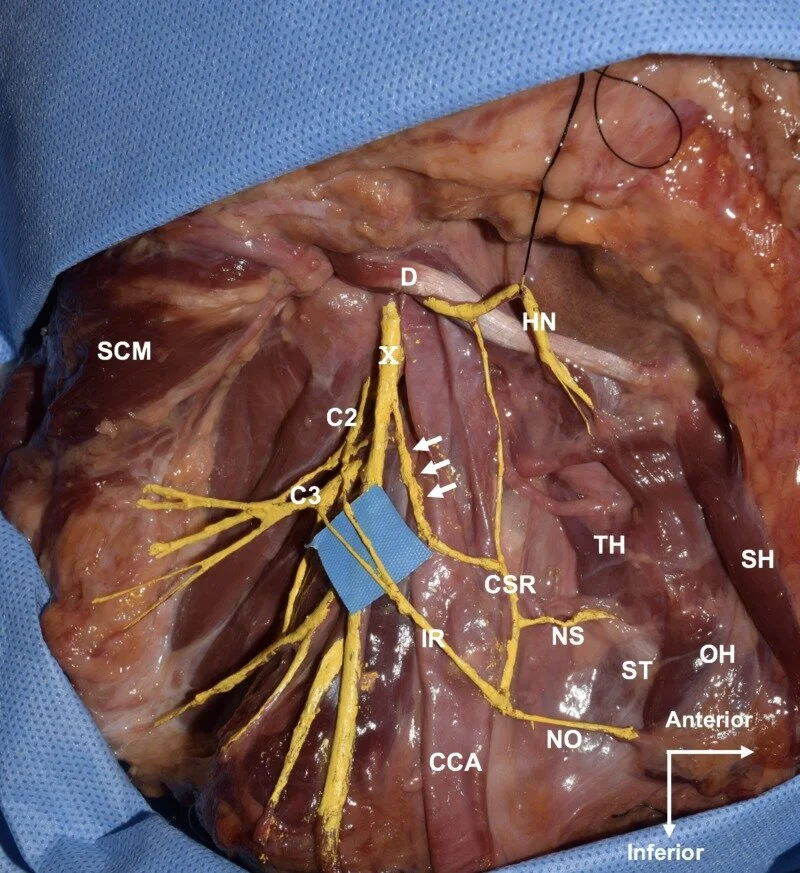

The ansa cervicalis is located around the carotid sheath and forms a neural loop, which consists of superior and inferior roots. It innervates the infrahyoid muscles. Anatomical variations of the superior root of the ansa cervicalis are uncommon. Herein, we present an extremely rare case of the superior root of the ansa cervicalis arising both from the hypoglossal and vagus nerves.